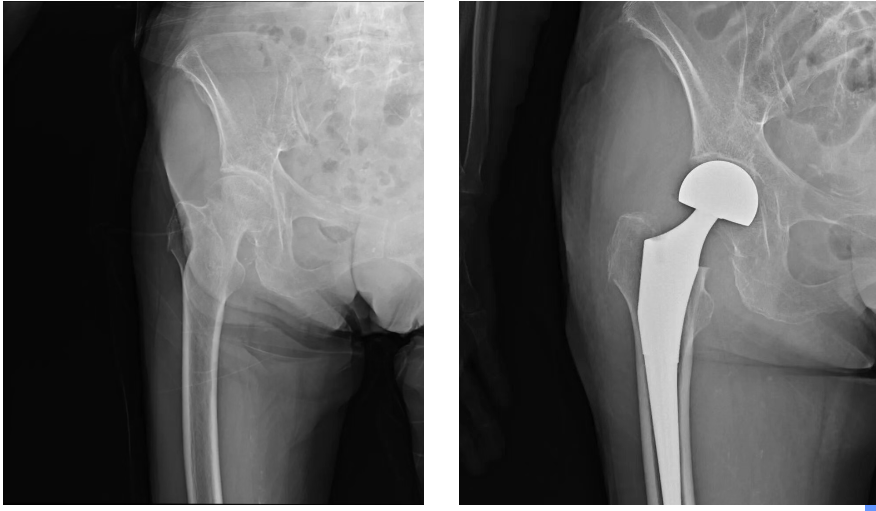

醫(yī)院立刻啟動多學科協(xié)作(MDT)機制。骨科、麻醉科、心血管內(nèi)科、呼吸與危重癥醫(yī)學科、神經(jīng)內(nèi)科等科室骨干迅速集結(jié),圍繞“保障安全、精準治療、快速康復”的核心目標,進行了多輪深入評估與討論,最終制定“右股骨頭置換術+右前臂高分子夾板固定”方案,并配套周密的圍手術期快速康復(ERAS)計劃。在手術團隊的精湛操作和嚴密配合下,手術順利完成。